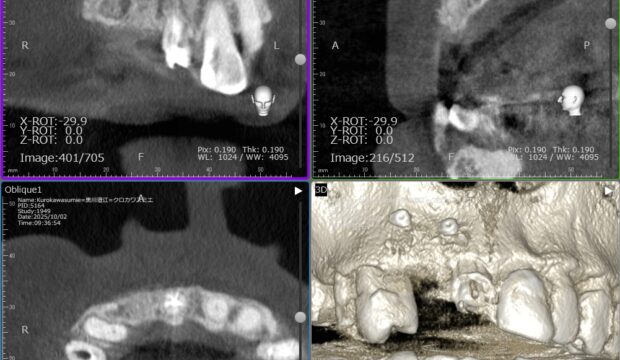

70代男性右の上下にロングスパンのブリッジが入っています。しばらくはそのまま定期検診を行っていましたが、右上7の根尖病巣に痛みを生じ、同じようにブリッジをすると負担がかかりますので、右上65にインプラント埋入を計画しました。

コンピュータガイドでしっかり位置決めを行います。やや上顎洞にかかるのでソケットリフトという手術を併用しました